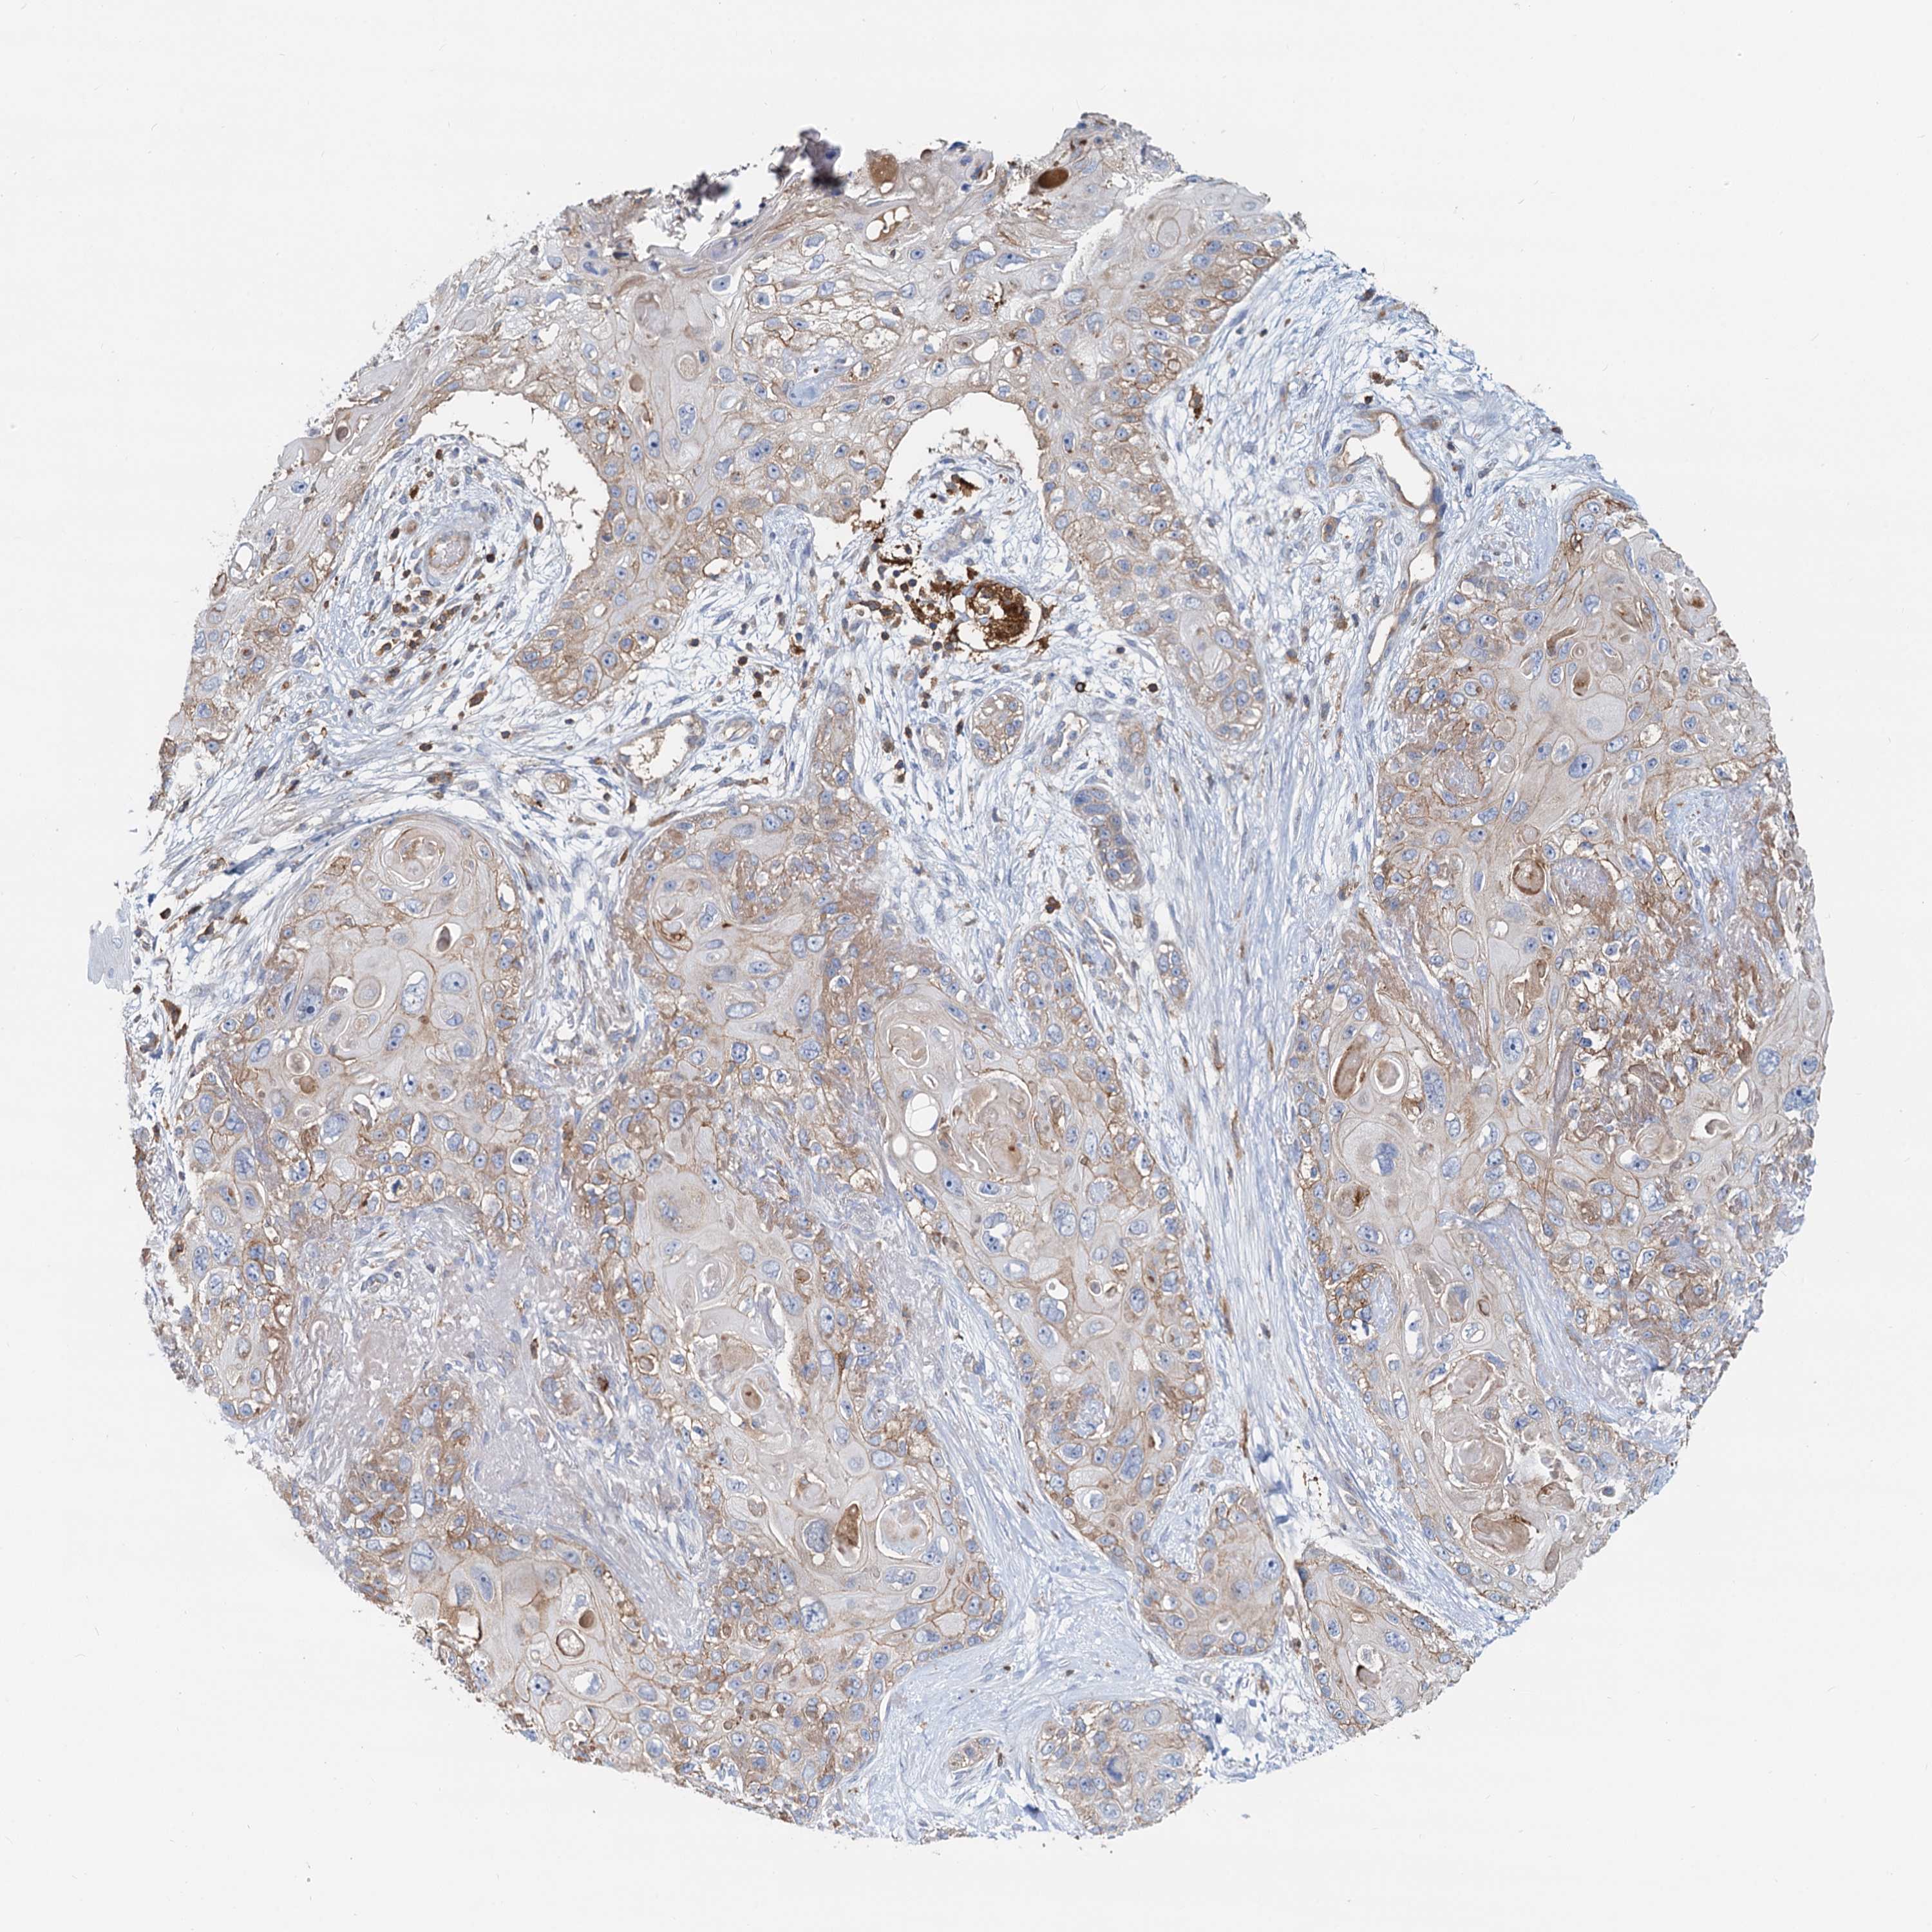

SKIN CANCER - Protein expressioni

A mouse-over function shows sample information and annotation data. Click on an image to view it in a full screen mode. Samples can be filtered based on level of antibody staining by selecting one or several of the following categories: high, medium, low and not detected. The assay and annotation is described here.

Antibody staining in the annotated cell types in the current human tissue is reported as not detected, low, medium, or high, based on conventional immunohistochemistry profiling in selected tissues. This score is based on the combination of the staining intensity and fraction of stained cells.

Each image is clickable and will lead to virtual microscopy that enables deeper exploration of all samples and also displays staining intensity scores, fraction scores and subcellular localization as well as patient and tissue information for each sample.

Antibody HPA040698

Squamous cell carcinoma, NOS